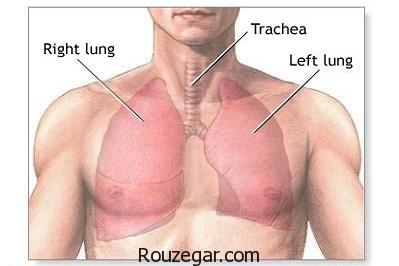

ذات الریه چیست؟

ذات الریه یا سینه پهلو اصطلاح عمومی است که برای توضیح بیماری های التهابی ریه به کار می رود. این بیماری معمولا به این دلیل ایجاد می شود که حفره های شش، کیسه های هوا در ریه ها، از چرک و مخاط پر می شوند. اما سینه پهلو می تواند به قسمت های مختلفی از ریه ها آسیب بزند. التهاب حفره های شش، توانایی ریه ها در گرفتن اکسیژن از هوا را محدود می کنند و درنتیجه موجب ناتوانی سیستم گردش خون می شود. مشکلات دیگری هم ممکن است اتفاق بیفتد. مثلا وقتی باکتری وارد خون می شود یا ریه ها به شدت ملتهب شده و بسته می شوند.